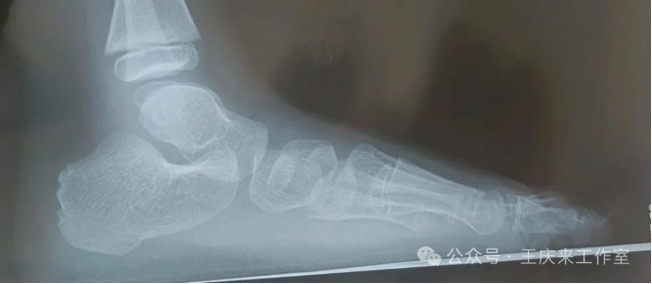

扁平足的檢測方法主要有兩種:足印法和影像學檢查。足印法簡單易行,通過觀察足印最窄區與足長的比例,可以初步判斷是否存在扁平足。影像學檢查則更為精確,通過足部X線檢查,可以測量足弓角度,明確足弓結構,從而準確判斷是否存在扁平足。

門診遇到一患者,女,15歲,學生,因“左踝及足疼痛1年余”,來我門診就診,詢問病史患者1年前出現左踝及足疼痛,行走或起步時疼痛明顯,休息后可見稍緩解。查體示雙側縱橫足弓消失,左踝及足背輕微腫脹。根據癥狀體征,診斷為“扁平足”。